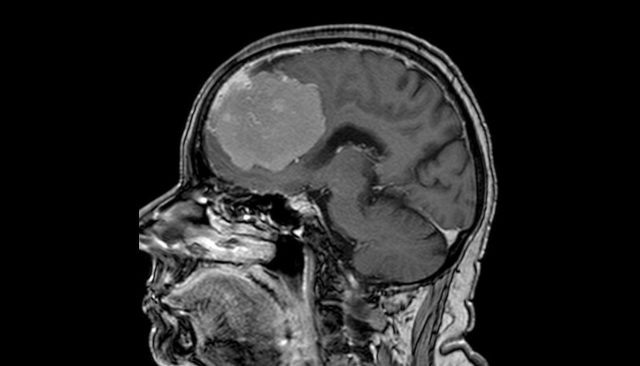

Фото предоставлено пресс-службой Минздрава Воронежской области

Женщину привезли в больницу с подозрением на инсульт. У неё ослабела правая рука. Также пациентке было тяжело говорить. Компьютерная томография показала, что инсульта нет. Однако результаты обследования оказались не менее тревожны. У пенсионерки нашли в обеих лобных долях мозга опухоль размером 6х7х8 см.

– Подобные новообразования так или иначе затрагивают важные участки мозга – кровеносные сосуды и зоны, отвечающие за речь и движение, – объясняют суть проблемы специалисты. – Дополнительное исследование с контрастом показало, что опухоль окутывала магистральные сосуды Велизиевого круга – переднюю мозговую артерию, а также прорастала в переднюю треть сагиттального синуса (один из наиболее крупных венозных коллекторов головного мозга) и закрывала его.